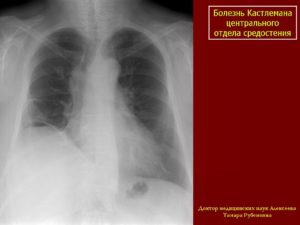

Кт и мрт диагностика болезни кастлемана

- Опухолевидные массы в средостении и/или прикорневой области.

- Изменения отмечаются преимущественно в среднем и заднем средостении и в прикорневой области (переднее средостение поражается редко)

Болезнь Кастлемана у женщины 30 лет.

На обзорной рентгенограмме грудной клетки видна опухоль с четко очерченными полициклическими контурами, локализующаяся в воротах правого легкого, которая не беспокоила больную и была выявлена случайно. Рентгенологически опухоль невозможно отличить от лимфомы и опухолей другой этиологии.

При гиалиново-сосудистом типе болезни Кастлемана выраженное контрастное усиление пораженных лимфатических узлов на КТ может помочь установлению типа лимфомы.